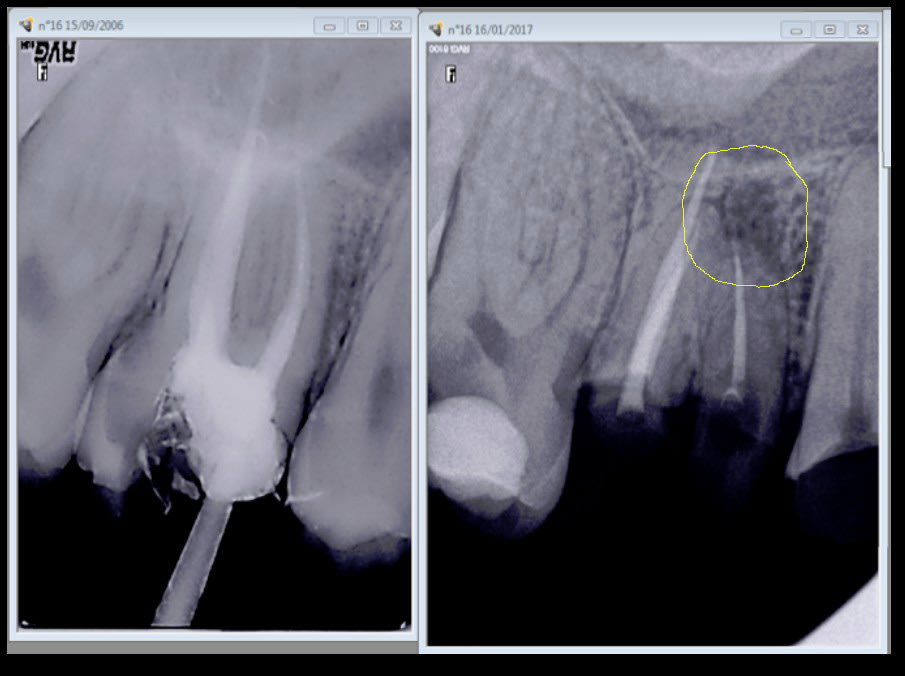

chicot29 écrivait:

> Meme sans digue et après 10 ans à l'air libre il n'y a pas de pèche à l'apex.

> Sauf si tu n'as pas traité le mv2.-))))

Radio 2 tu vois pas de pèche ?

Si justement. C'est bien le mv2 non traité. -)

Quand je vais la virer c'est ce que révèlera l'autopsie de cette racine. -)

mais bon ca aurait pu etre plus grave si j'avais fait une couronne dessus hein casa ? -)))

Mais dans ce cas particulier c'est pas cette dent qui 10 ans après pose problème c'est la 15.-)

La couronne aurait au moins eu le mérite de protéger ce qui restait de la dent au départ. -)

Quand on parle du loup. -)))

Merde endo et couronne faites en 2011 pèche en 2017.

Quizzzzz : c'est la faute à pas de digue ? -))))